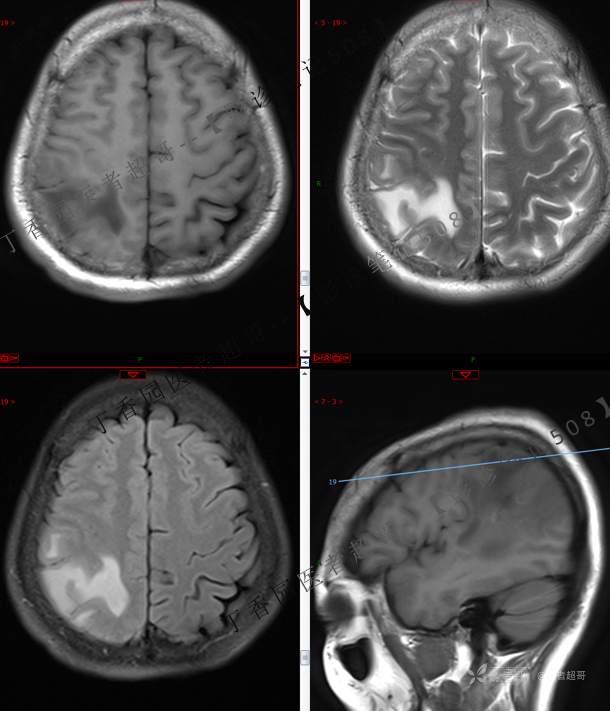

【影诊笔记508】同病异影,个人感觉有难度,欢迎分析,领丁当!有详细术程及病理!

主 诉:突发一过性意识不清伴肢体抽搐5天余。

现病史:患者5天余前无明显原因及诱因出现一过性意识不清,伴肢体抽搐,持续约2-3分钟,后意识逐渐恢复,无明显头痛头晕,无恶心呕吐,无肢体抽搐,无呼吸困难,无二便失禁,后就诊于当地医院,行颅脑CT示“颅内占位性病变”,予以药物对症治疗,具体不详,门诊以“颅内占位性病变”,收入我科。患者自发病以来,未进饮食,近期体重无明显变化。